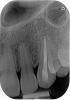

Nafania Опубликовано 18 мая, 2011 Автор Поделиться Опубликовано 18 мая, 2011 Сегодня сняли коронку, опять качали головами, что коронка хорошая, головные боли не от нее и зубы подвинутся не могли. Субъективно сразу стало лучше. Меня очень беспокоят трещины на зубах (сильно заметны при ярком солнце, снять фото пока не удалось). Сделали снимки передних верхних зубов - сказали все нормально , но меня беспокоит один зуб. Уважаемые врачи, прокомментируйте, пожалуйста, есть ли повод для беспокойства Здесь снимок трещин (правда не все видны, их гораздо больше ) и коронки - на месте "5". Ссылка на комментарий

Nafania Опубликовано 19 мая, 2011 Автор Поделиться Опубликовано 19 мая, 2011 (изменено) От трещин в эмали мне порекомендовали использовать мусс GC и сказали, что трещины есть у всех. А вопрос количества - дело субъективное. Хотя я и остаюсь при своем мнении, что коронка "добавила" это количество . Подскажите, пожалуйста, есть ли повод к беспокойству за передние зубы на основании рентгеновских снимков? Мне сказали, что все нормально (разговор велся по-английски - и здесь все всегда - нормально). Но при проверке (не уверена как называется точно - когда в чем-то смоченный кусочек марли прикладывают к зубам) один зуб реагировал не сразу, как остальные, а с примерно 4-секундной задержкой. (Справедливости ради надо сказать, что этот зуб некоторое время назад стал темнее, чем другие) Внизу снимок импланта и "3" до установки коронки. В верхнем сообщении - снимки после установки.И еще вопрос (прошу прощения, если уже задавался раньше, но весь форум я прочитать пока не успела). КАК пациенту определить что коронка "правильная"? В моем случае, как определить "правильность" контакта с соседними зубами? У меня это первый опыт, мне сказали, что несколько дней может идти привыкание - и я честно ждала А внешне - все выглядело почти прекрасно...Теперь жалею... Надо было на следующий же день снимать...Сейчас стоит "healing" абатмент, и зубы явно "подвинулись" назад, головные боли прошли! Честно сказать, боюсь опять ставить коронкуИзвините, очень много написала. Спасибо, что дочитали. Изменено 19 мая, 2011 пользователем Nafania Ссылка на комментарий